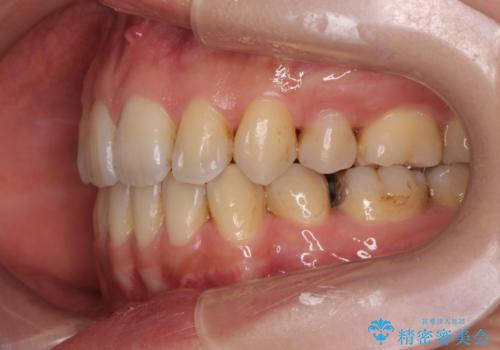

歯並びの改善と共に、歯ブラシがしやすくなった!と喜んでいただくことができました。

- 八重歯・がたつきのある歯並びの改善を求めて来院されました。

全部の歯が入り切るスペースがなかったため、小臼歯4本を抜去しワイヤーを用いたマルチブラケット矯正を選択しました。